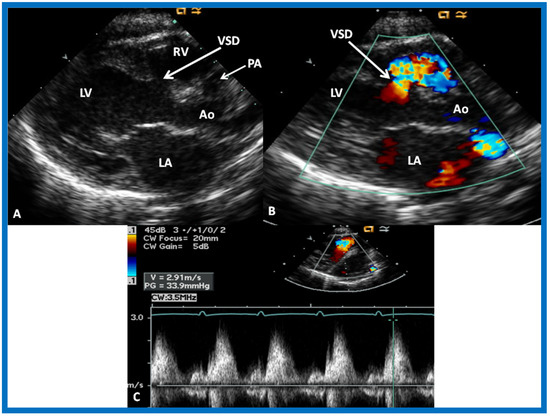

The relationship of the great arteries is examined next in order to classify them into various types [41]. The relationship of the great arteries is established by following the vessels arising from the ventricles until pulmonary bifurcation or aortic arch. In Type I patients with normally related great arteries, the aorta arises from the LV (Figure 20), while in Type II patients with transposition of the great arteries, the PA arises from the LV (Figure 21 and Figure 22). In Type III patients, it may be little more difficult to assign the great artery relationship, and sometimes angiography is needed. In type IV with truncus arteriosus, the limited data [22] suggest that this can be done by echocardiography (Figure 23 and Figure 24).

Selected video frames from precordial long axis views of a neonate with tricuspid atresia with normally related great arteries demonstrating enlarged left atrium (LA) and left ventricle (LV), a small right ventricle (RV) and a moderate sized ventricular septal defect (VSD) (thick arrow) on 2D (A) and color flow (B) imaging. Turbulent flow (B) with a Doppler flow velocity of 2.91 m/s by continuous wave Doppler (C) suggests some restriction of the VSD. Ao, Aorta; PA, pulmonary artery. Reproduced from Rao P.S. [39].

Then, the ventricular septum is evaluated; the ventricular septum is intact in most Type Ia cases. In children with Type I (normally related great arteries), the VSD supplies pulmonary blood flow (Figure 20) while in patients with Type II (transposition the great arteries), the VSD allows blood to flow into the systemic circuit (Figure 21 and Figure 22). In Type I patients, the VSD is demonstrated by 2D (Figure 20A) and the left to-right shunt across it by color (Figure 20B), pulsed and CW (Figure 20C) Doppler signals. Interrogation of the right ventricular outflow tract and pulmonary artery region is performed; peak Doppler flow velocity across the right ventricular outflow tract and pulmonary valve is helpful in identifying obstruction across these sites. The Doppler data from the VSD and RVOT are also helpful in estimating of pulmonary artery pressures. In these Type I babies, the 2D size of the VSD and the peak Doppler flow velocity across it are useful in quantifying the size of the VSD (Figure 20); the higher the VSD Doppler velocity, the smaller the defect. However, in patients with pulmonary hypertension, severe infundibular or valvar pulmonary stenosis, the VSD Doppler velocities do not reflect the size of the VSD. Barring these exceptions, right ventricular and pulmonary arterial pressure may be estimated using modified Bernoulli equation (RV/PA systolic pressure = systolic BP − 4V2).